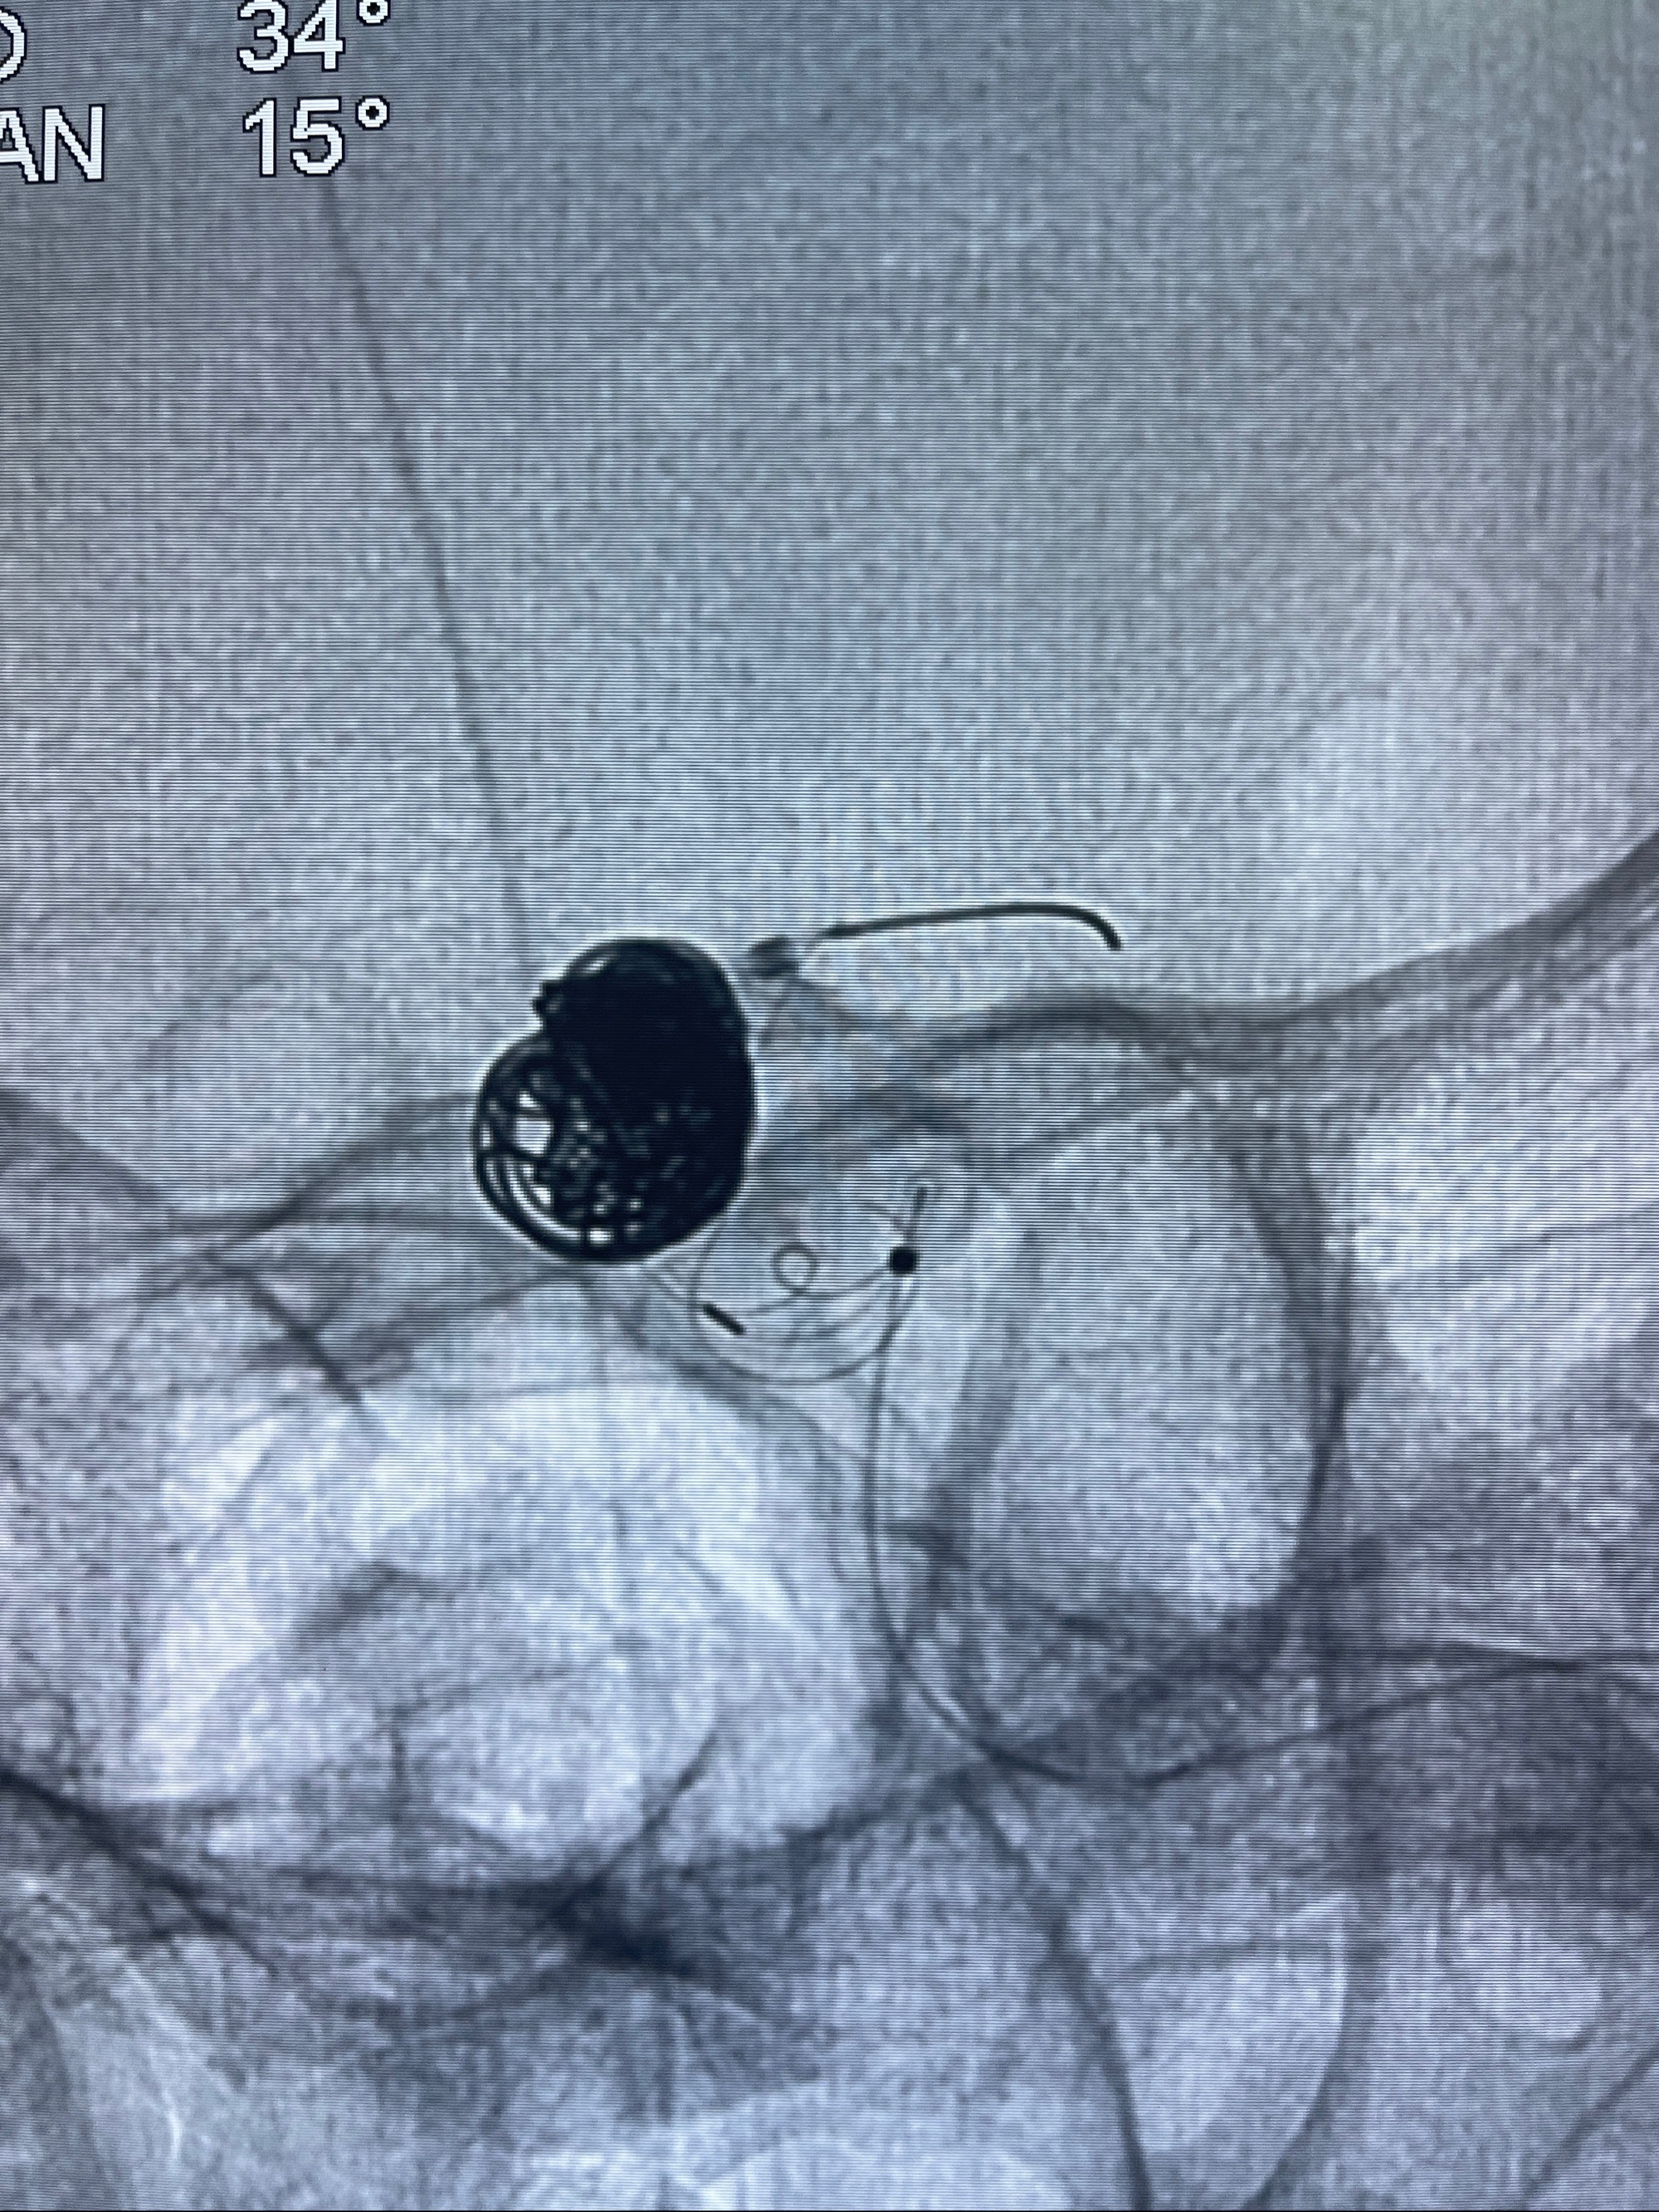

- Tubridge 4.0-20mm密网支架

术后3D显示支架贴壁佳